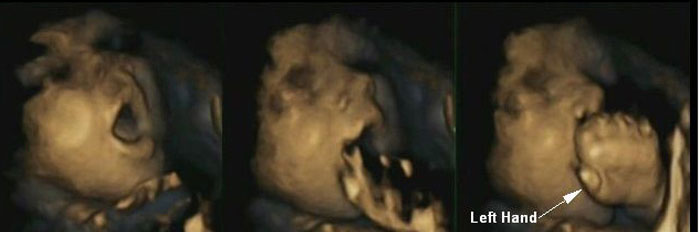

Using 4-d scans psychologists found, for the first time, that fetuses were able to predict, rather than react to, their own hand movements towards their mouths as they entered the later stages of gestation compared to earlier in a pregnancy.

By 36 weeks the fetuses were observed opening their mouths significantly more frequently before touching them, suggesting that later in pregnancy they were able to anticipate that their hands were about to touch their mouths, rather than reacting to the touch of their hands, the researchers said.

Increased sensitivity around a fetus’ mouth at this later stage of pregnancy could mean that they have more “awareness” of mouth movement, they added.